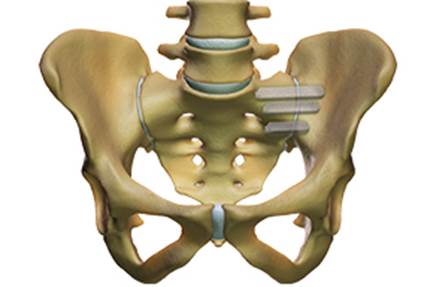

Surgical treatment of the painful SI joint is indicated only in cases where conservative therapy has failed for longer than 6 months. If the chronic SI joint pain persists, minimally invasive surgery can be performed: it consists of the percutaneous placement of three triangular titanium implants that block the ilium and sacrum bones, blocking the SI joint in all its degrees of freedom.

Characterization of percutaneous surgical fusion of the left sacro-iliac

joint by means of 3 titanium implants with triangular profile.

Dr. Morgenstern is an accredited surgeon for the percutaneous fusion of the sacroiliac joints.